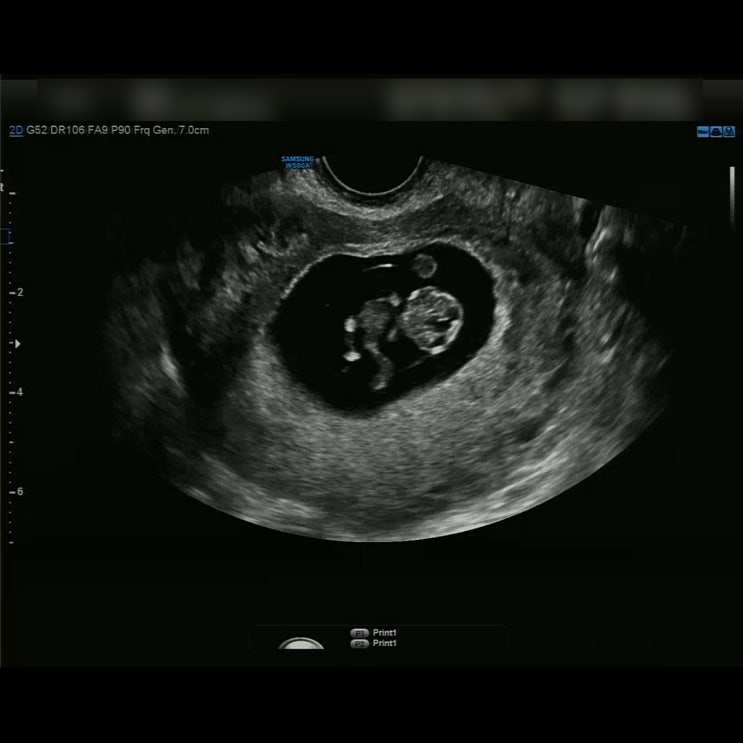

임신일기 # 11~20주차(기형아검사, 목투명대, 성별)

35주차에 들어서서 더듬더듬 써보려고하니 여러가지 많이 빼먹은것들도있고 그렇네요 지금생각해보면 평생 ...

임신일기 # 6~10주차(조리원예약, 성별테스트기, 입덧)

임신일기 # 6~10주차(조리원예약, 성별테스트기, 입덧) 임신일기 # 6~10주차(조리원예약, 성별테스트기, 입...